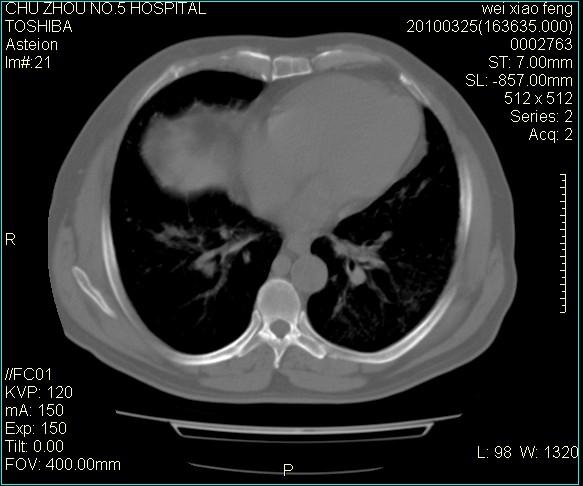

标题: CT25347:男,60岁,反复咳、痰、喘3月,加重3天。诊断??? [打印本页]

男,60岁,反复咳、痰、喘3月,加重3天。

右肺中叶结节影为原发灶,考虑右肺中叶周围型肺癌并淋巴道转移